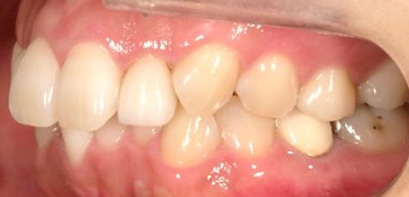

乱ぐい歯、でこぼこがとても酷い状態になります。歯が前後的に重なってしまっている、八重歯になっているなどがこのジャンルに入ります。

顎の大きさと歯の大きさのギャップが大きく、時には歯を抜かないと矯正治療ができない場合もあります。当院では治療期間が長くなるが抜かない治療方針など、一つの治療プランだけでなく、さまざまな可能性の治療方針を説明させて頂くよう心掛けております。こういった考え方はインフォームド・チョイスと言われ近年大切にされている考え方と言われております。